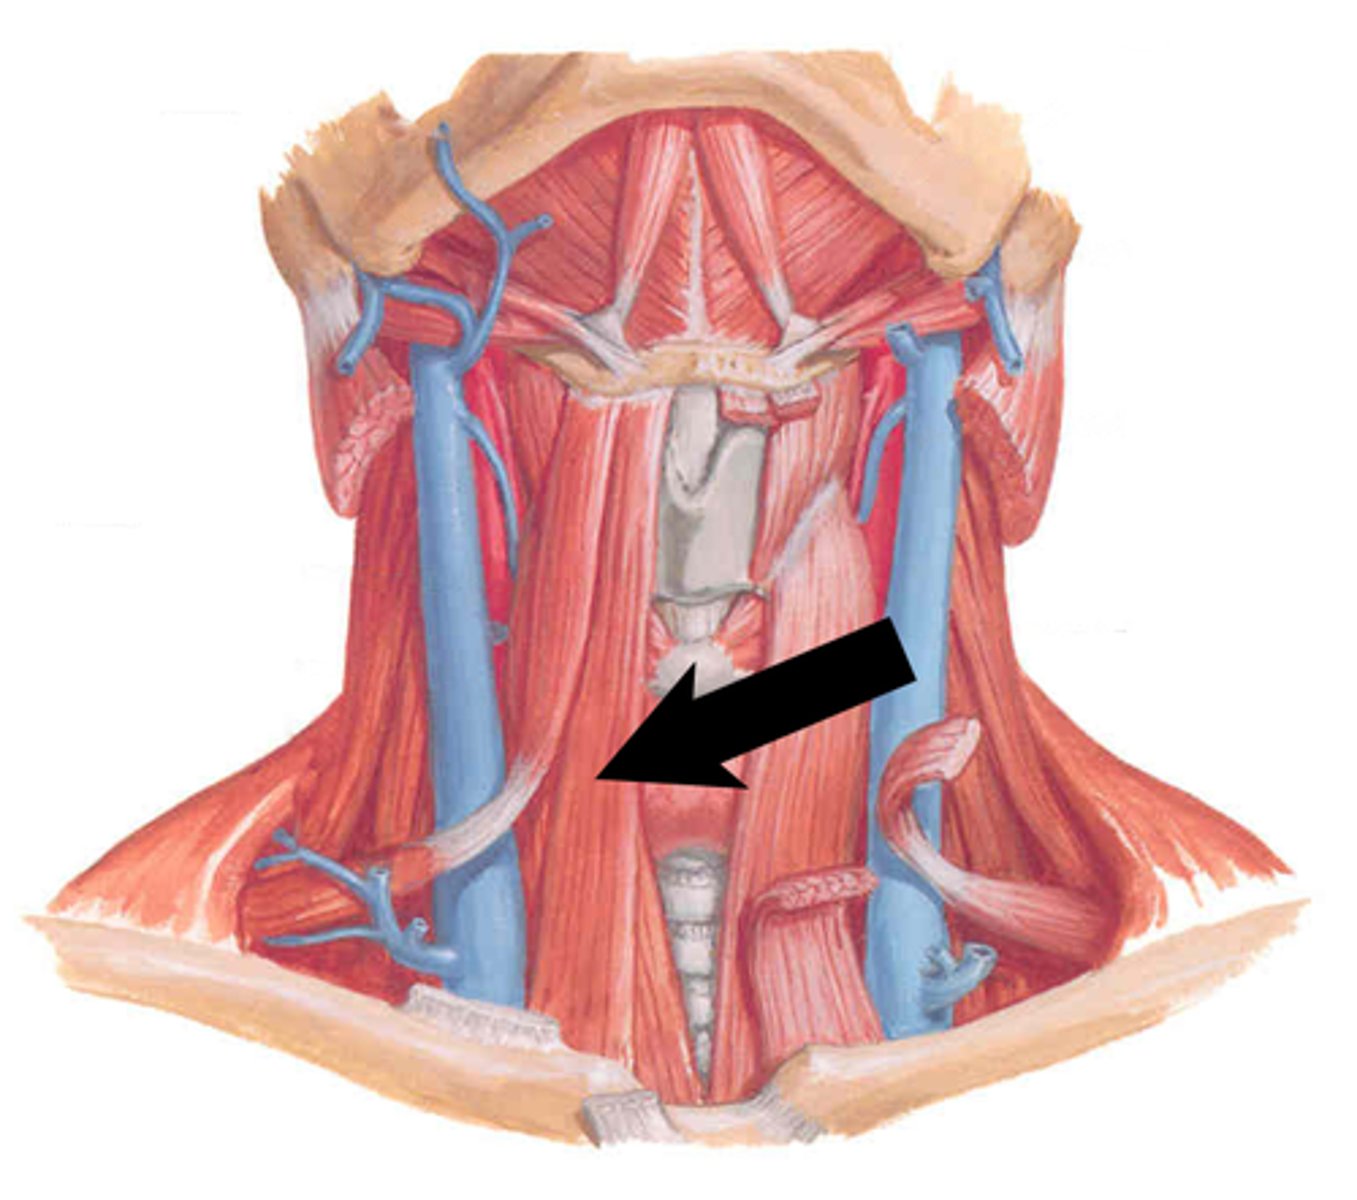

Sternohyoid m.

Origin: Clavicle/sternum

Insertion: Hyoid

Action: Depress

Omohyoid (two bellies) m.

Origin: Clavicle/scapula

Insertion: Hyoid

Action: Depress

Thyrohyoid m.

Origin: Thyroid cartilage

Insertion: Hyoid

Action: Depress, Elevate larynx

Sternothyroid m.

Origin: Sternum

Insertion: Thyroid Cartilage Action: Depress

Sternocleidomastoid m.

Origin: Sternum/Clavicle

Insertion: Mastoid Process

Action: Flex, Rotate